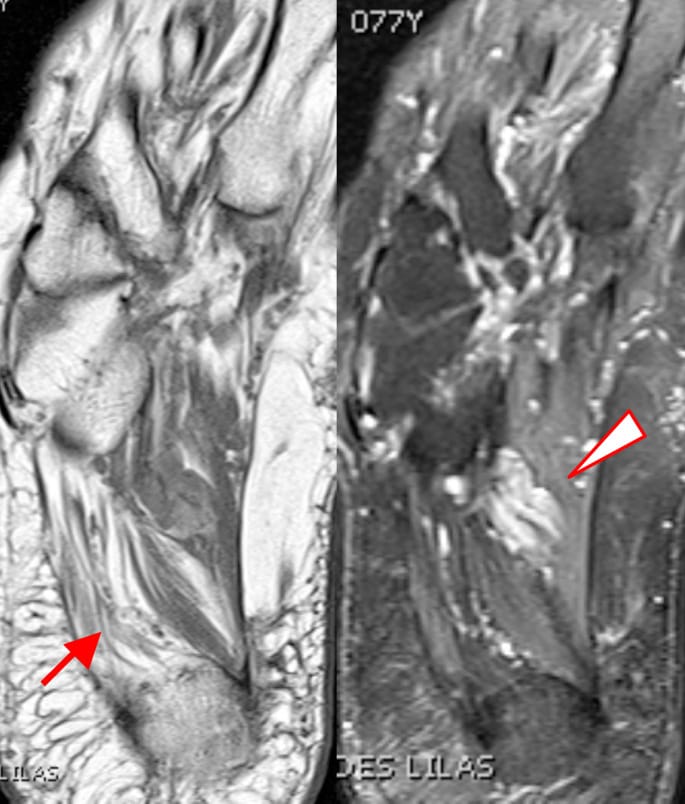

Syndrome de Baxter

Pierre Le HirClinique des Lilas (93)